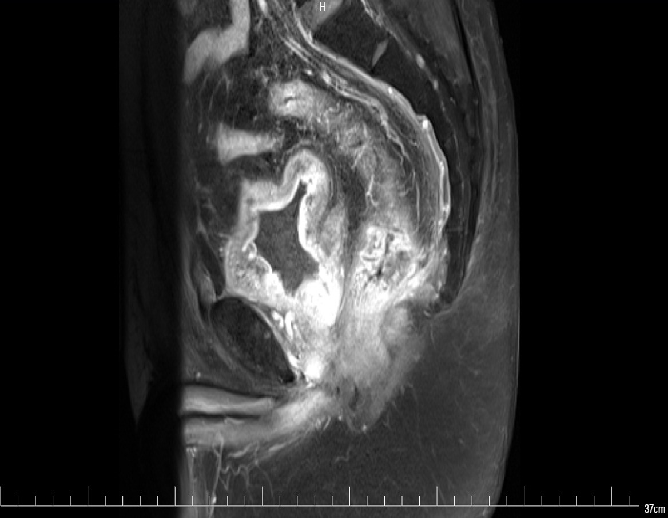

MR:1、直肠癌(T3可能),与右侧肛提肌关系密切,考虑1、炎性渗出粘连2、侵犯待排2、慢性膀胱炎3、前列腺增生。

2017-09 MR: